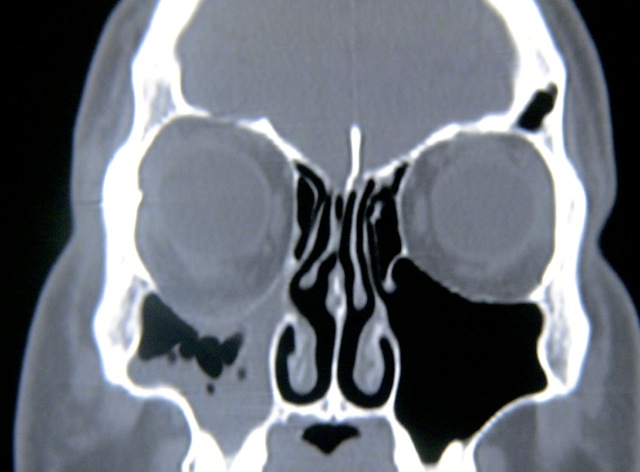

- CT imaging showing contraction of maxillary sinus

Imaging

Radiographic findings are pathognomonic and required to make the diagnosis of silent sinus syndrome.[1][3][12] CT imaging characteristically shows ipsilateral maxillary sinus shrinkage with areas of focal bone loss and increased radiolucency due to enlarged fat density in the pterygomaxillary fossa.[1][3][6]

The orbital floor is typically inferiorly displaced and may be associated with concavity of the medial and posterolateral walls of the maxilla as well.[3][6] The radiographic appearance of the orbital floor is the point of some debate. Most authors exclusively describe patchy demineralization[3] and decreased bone density[6] or dramatic thinning[1] of the bony orbital floor. In the Rose et al. 2003 series, however, 3 of 12 patients instead were noted to have thickened bone of the orbital floor.[3] Dr. Rose later clarified this observation, explaining that one would expect hyperostosis and orbital floor thickening only in cases where mucosal inflammation had been very longstanding.[10]

Other radiographic findings include nasal septum deviation to the affected side, noted in 32% to 83% of cases,[3][7][9] and anomalous direction of middle turbinate.[3] Rarely, concurrent collapse of a neighboring, ipsilateral ethmoid sinus has been documented.[3][13][21]